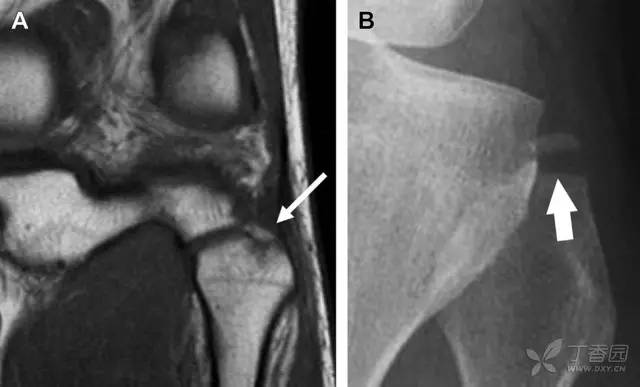

胫骨平台内侧皮质骨撕脱性骨折,被称为内侧 Segond 骨折或反向 Segond 骨折(图 5)。这种骨折的旋转机制与 Segond 骨折相反,该骨折与后交叉韧带断裂及内侧半月板损伤相关。

图 5 一位足球运动员的反向 Segond 骨折

A 正位片示关节线处的胫骨内侧见一细小骨折片(箭头)。B MRI 冠状位 T1 加权像示骨折片出现在内侧副韧带关节囊附着处(方框)。

为胫骨前内侧受到直接*力暴**作用,发生在腓骨茎突的横形骨折,可表现为弓形信号(图 6)。可伴发前交叉韧带或后交叉韧带的断裂。如果弓形信号被忽视或未处理,前交叉韧带的重建将失败。

图 6 跌倒后发生腓骨茎突骨折

A MRI 冠状位 T1 加权像示腓骨茎突撕脱性骨折(箭头)。弓状韧带附着于骨折碎片,而联合腱绕过外侧附着于其上。B 正位片见横形骨折线(箭头)。

约 6% 的后交叉韧带断裂与撕脱性骨折有关。X 线片特征表现为膝关节侧位片上可见大小不等的三角形骨折碎片移位到关节内(图 7)。

图 7 车祸后的后交叉韧带撕脱骨折

A 侧位片示后关节间隙见一移位的三角形骨折碎片(箭头)。B 矢状位 MRI 图像示骨折碎片(实箭头)附着于后交叉韧带上(空箭头)。

膝关节外侧由髂胫束、股二头肌和肌腱、外侧关节囊韧带及外侧副韧带组成。外侧副韧带对抗过度内旋*力暴**,维持膝关节稳定。当内旋*力暴**足够大时,韧带断裂或腓骨头撕脱性骨折就发生了。在 X 线片上,骨折线垂直于股骨头外侧(图 8)。

图 8 过度伸展引起的腓骨头撕脱性骨折

A 侧位片示腓骨头外侧的垂直骨折(箭头)。B MRI 冠状位 T1 加权像示骨折碎片同时附着于外侧副韧带(箭头)和弓状韧带上(弧形箭头)。